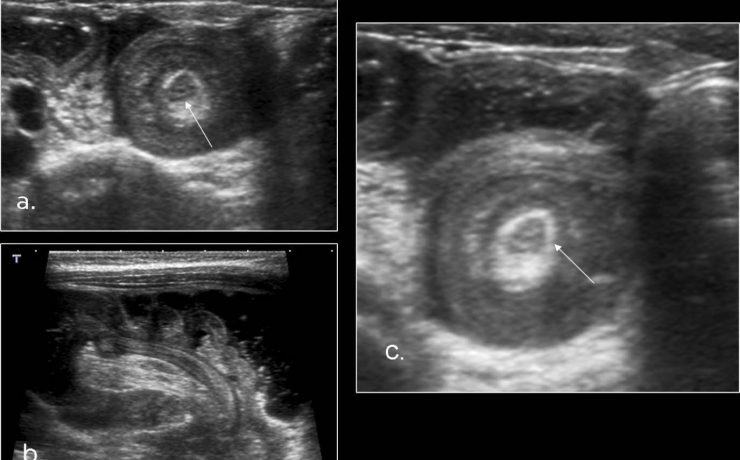

El estudio ultrasonográfico de la vía biliar requiere que el paciente este en ayunas de 6 horas, puesto que la ingesta de alimentos, sobre todo de naturaleza grasa, provoca la contracción o el colapso de la vesícula biliar, también reduce el gas intestinal que dificulta la evaluación ecográfica de la